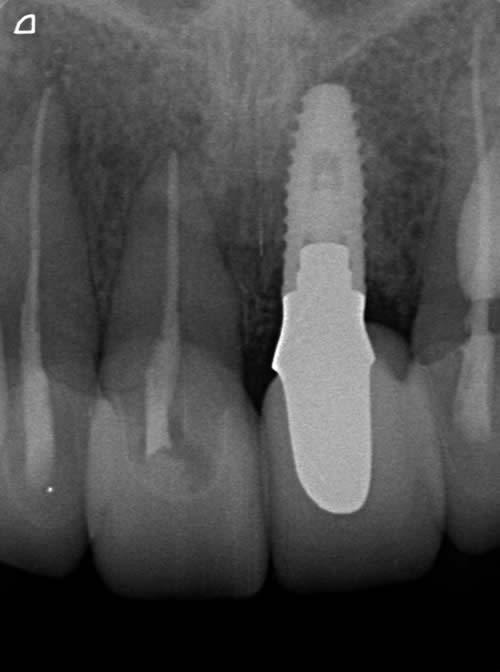

< 症例2 >

- 治療期間:8ヶ月

- 治療回数:12回

- 治療歯数:1歯

- 費用:インプラント治療:47万円 上部セラミック:89,000円

- リスク:メンテナンスを怠ると、インプラント周囲炎になる可能性があります。

- インプラント手術には合併症が伴う場合があります。

- 治療期間は治癒の状態により前後する場合があります。